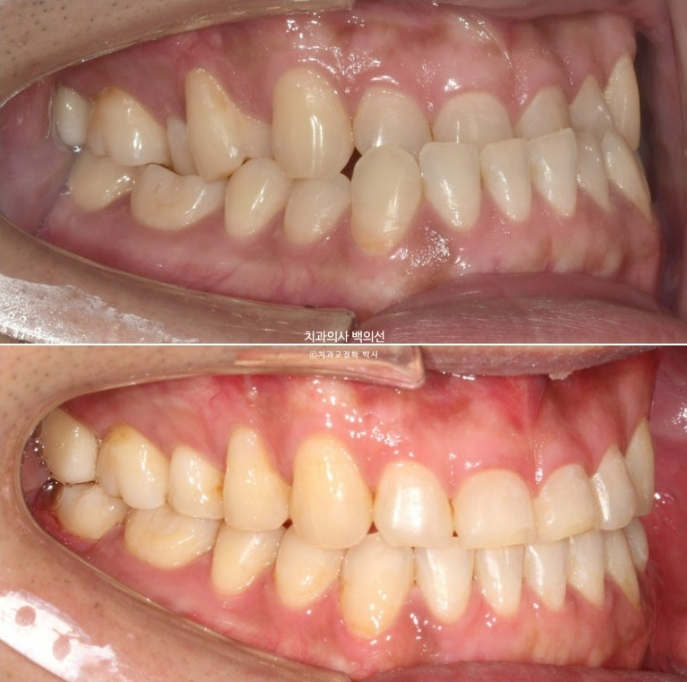

23년 7월 앞니 거꾸로 물림을 교정으로 해결하고자 내원하신 30대 남성분

아랫니에 가려서 잘 보이지는 않지만

23.07

앞니 마모가 상당히 심합니다.

거꾸로 물리는 상태로 오래 지내오다보니, 아랫니와 닿는 부분들이 마모가 된 것입니다.

마모도를 보면 교합력도 상당히 센 편임을 알 수 있습니다.

23.07~25.04

중심선은 잘 맞으며

어금니 교합은 좋습니다.

철사유지장치까지 부착된 모습입니다.

앞니 거꾸로 물리는 반대교합은 해소가 되었고